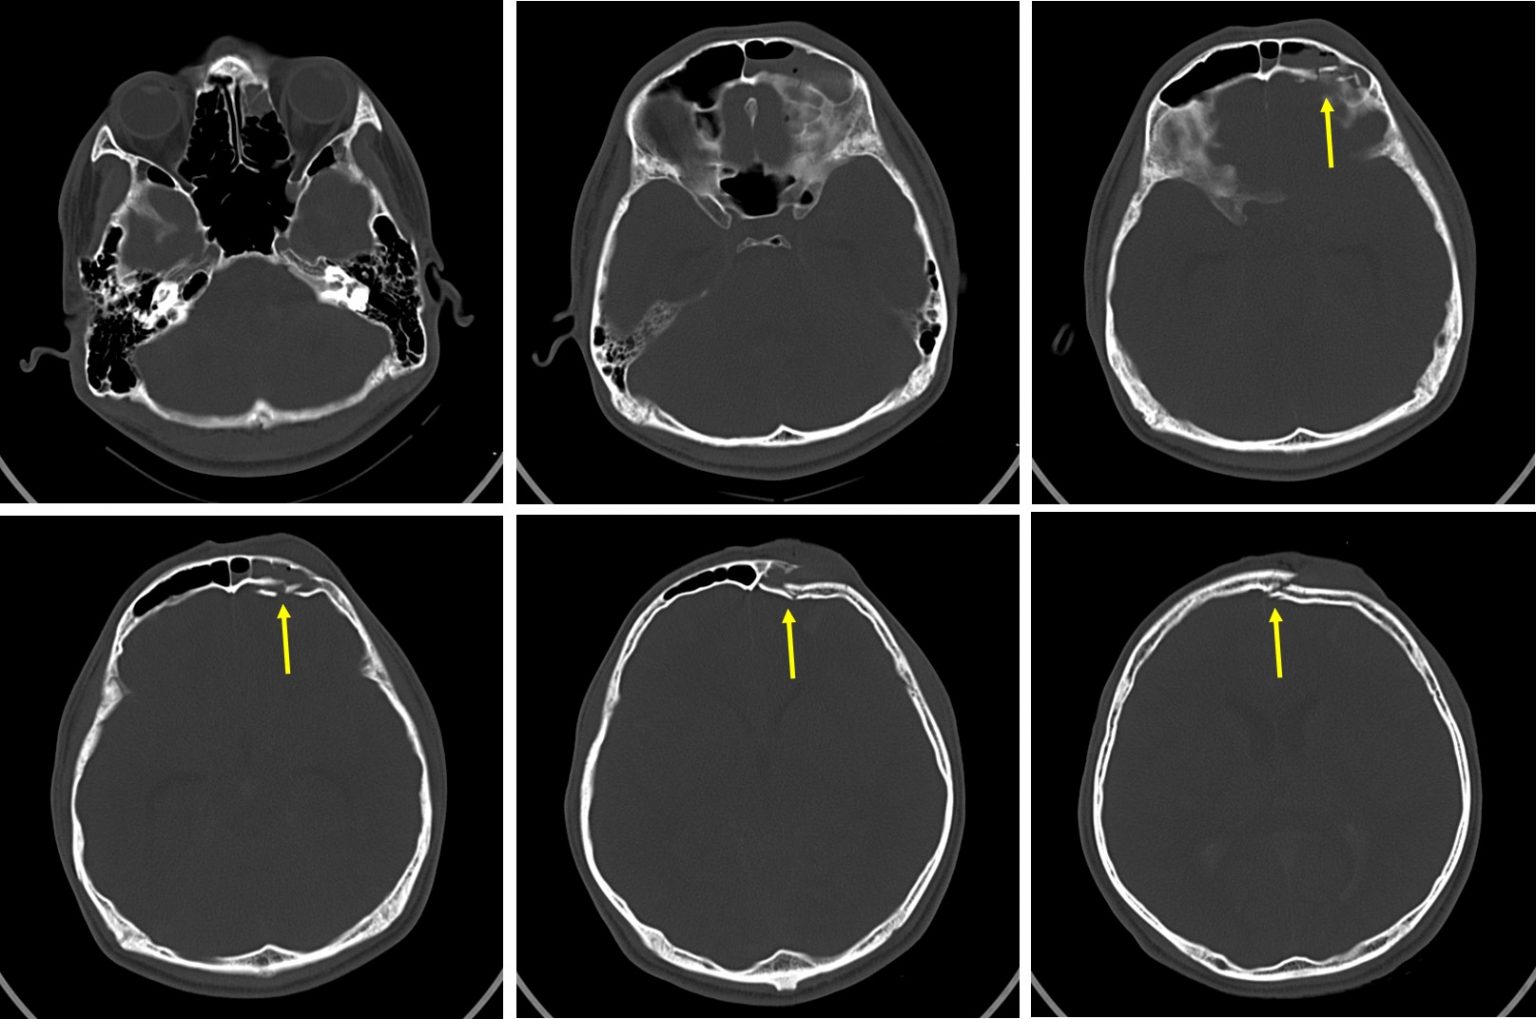

Frontal bone fracture and frontal sinus injury Radiology Cases Face Bones Ct This head and neck anatomy atlas is an educational tool for studying the normal anatomy of the face based on a contrast enhanced multidetector computed tomography imaging (axial and coronal. Labelled radiographs and ct/mri series teaching anatomy with a level of detail appropriate for medical students and junior residents. The labeled structures are (excluding the correct. For facial ct, we. Face Bones Ct.

From www.researchgate.net

Axial CT bone window of skull base from inferior to superior aspect Face Bones Ct This head and neck anatomy atlas is an educational tool for studying the normal anatomy of the face based on a contrast enhanced multidetector computed tomography imaging (axial and coronal. The labeled structures are (excluding the correct. For facial ct, we rely on two primary window settings: The labeled structures are (excluding the correct side): Labelled radiographs and ct/mri series. Face Bones Ct.